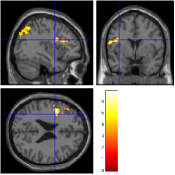

Concerning the Lc-Rc contrast on the data acquired with , Fig. 7 [top] shows that all reconstruction methods enable to retrieve the expected activation in the right precentral gyrus. However, when looking more carefully at the statistical results (see Tab. 2), our pipeline and especially the 4D-UWR-SENSE algorithm retrieves an additional cluster in the right middle frontal gyrus. On data acquired with , the same Lc-Rc contrast elicits similar activations, i.e. in the same region. As demonstrated in Fig. 7 [bottom], this activity is enhanced when pMRI reconstruction is performed with our pipeline. Quantitative results in Tab. 2 confirm numerically what can be observed in Fig. 7: larger clusters with higher local -scores are detected using the 4D-UWR-SENSE algorithm, both for and . Also, a larger number of clusters is retrieved for using wavelet-based regularization.

In order to investigate the smoothing effect introduced by our algorithm, spatial smoothing in the pre-processing pipeline has been turned off and statistical results are illustrated in Fig. 7 [right] and Tab. 2 (Unsmoothed 4D-UWR-SENSE). As expected, qualitative and quantitative results show that deactivating the spatial smoothing gives slightly higher -score values for activation maxima. However, smaller activated clusters are detected compared to results obtained based on smoothed data. As regards the temporal regularization effect, statistical results (not shown here) obtained with 3D-UWR-SENSE reconstructed images show intermediate performance which lies between those of the 2D (UWR-SENSE) and 4D (4D-UWR-SENSE) versions. Indeed, such a regularization helps improving the BOLD signal contrast which allows us to retrieve higher activation peaks.

| mSENSE | UWR-SENSE | 4D-UWR-SENSE | Unsmoothed 4D-UWR-SENSE | |

|---|---|---|---|---|

|

|

|

|

|

|

|

|

|

| cluster-level | voxel-level | |||||

| p-value | Size | p-value | T-score | Position | ||

| mSENSE | 79 | 6.49 | 38 -26 66 | |||

| UWR-SENSE | 144 | 0.004 | 5.82 | 40 -22 63 | ||

| 21 | 0.064 | 4.19 | 24 -8 63 | |||

| 4D-UWR-SENSE | 189 | 0.001 | 7.03 | 34 -24 69 | ||

| 53 | 0.001 | 4.98 | 50 -18 42 | |||

| 47 | 0.001 | 5.14 | 32 -6 66 | |||

| Unsmoothed 4D-UWR-SENSE | 112 | 0.001 | 7.26 | 34 -24 69 | ||

| 21 | 0.001 | 4.77 | 32 -6 66 | |||

| 19 | 0.001 | 4.98 | 50 -18 42 | |||

| mSENSE | 0.006 | 21 | 0.295 | 4.82 | 34 -28 63 | |

| UWR-SENSE | 33 | 0.120 | 5.06 | 40 -24 66 | ||

| 4D-UWR-SENSE | 51 | 0.006 | 5.57 | 40 -24 66 | ||

| Unsmoothed 4D-UWR-SENSE | 25 | 0.001 | 5.7 | 40 -24 66 | ||

Fig. 8 reports on the robustness of the proposed pMRI pipeline to the between-subject variability for this motor contrast. Since sensory functions are expected to generate larger BOLD effects (higher SNR) and appear more stable, our comparison takes place at . Two subject-level Student’s -maps reconstructed using the different pMRI algorithms are compared in Fig. 8. For the second subject, one can observe that the mSENSE algorithm fails to detect any activation cluster in the right motor cortex. By contrast, our 4D-UWR-SENSE method retrieves more coherent activity for this second subject in the expected region.